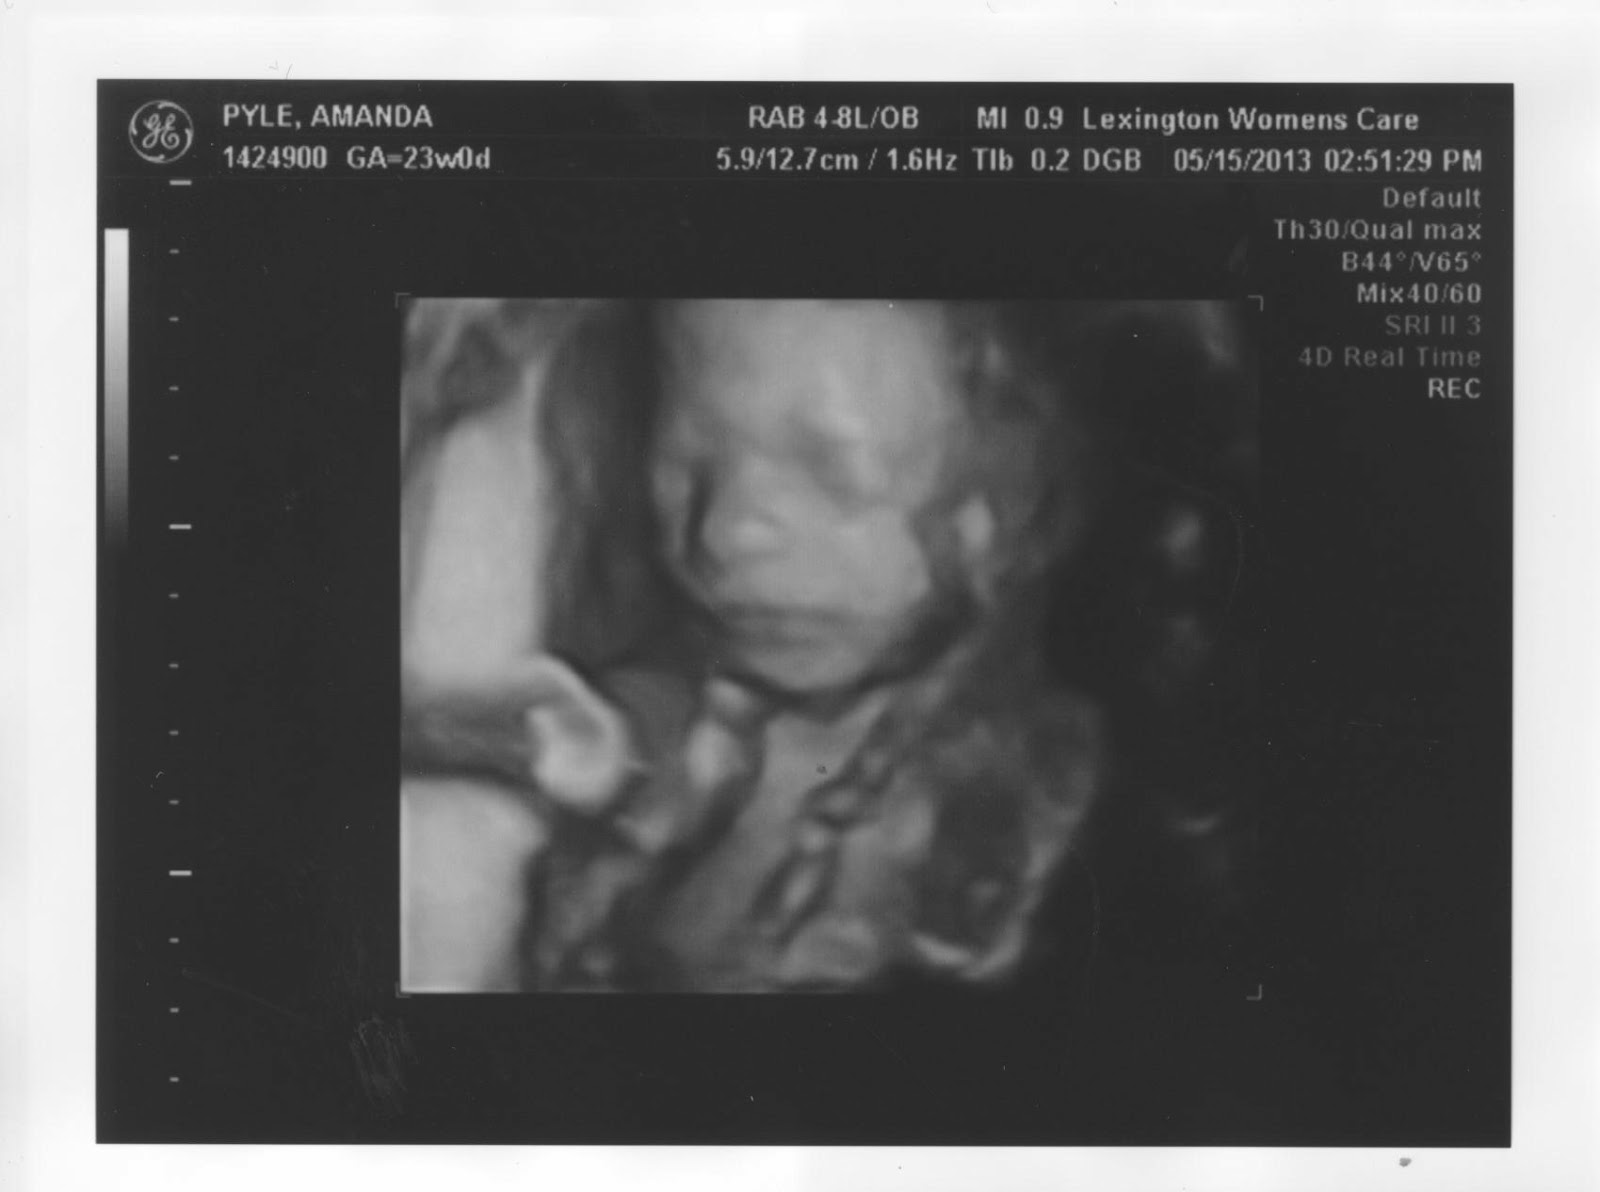

And despite him moving so much and constantly facing away from the camera OR covering his face, we were able to get a few other good shots! Here's our handsome man:

I'm pretty sure he was getting a little mad with us - check out that wrinkle in the forehead:)

Already posing for the camera!

Yes, that's the umbilical cord wrapped around his neck, and no it's nothing to worry about (at least that's what they told us)!